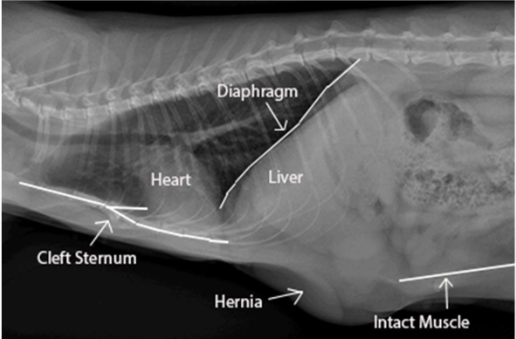

What can be seen here?

Here is the rupture visualised

Discuss traumatic abdominal rupture?